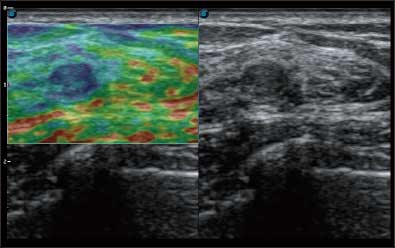

全新算法处理射频信号 不可靠区域自动剔除 支持定量分析 压力曲线保证重复性